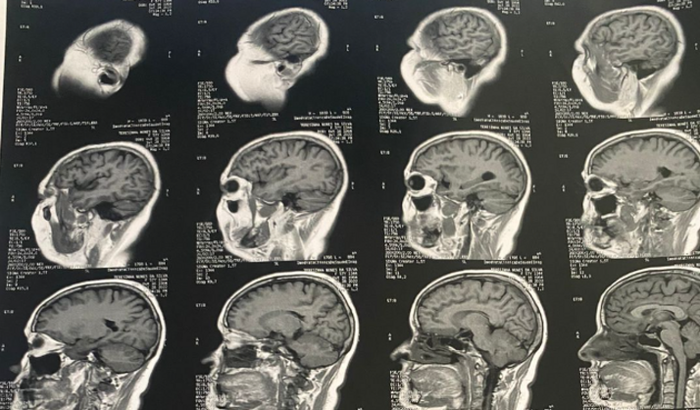

Sou o Luiz, irmão da Tereza,que recentemente descobriu um tumor em seu cérebro, passou por diversos exames e foi encaminhada ao SUS. Nessa última semana, Tereza relatou problemas na vista e fez mais exames, essa perca de vista é relacionada ao tumor que tem em seu cérebro. Se não for feita uma cirurgia de emergência, Tereza perderá totalmente sua visão. O cirurgião do SUS disse que a cirurgia só poderá ser feita daqui a 9 semanas , pois há muitas pessoas também esperando, e até lá Tereza pode perder sua visão.